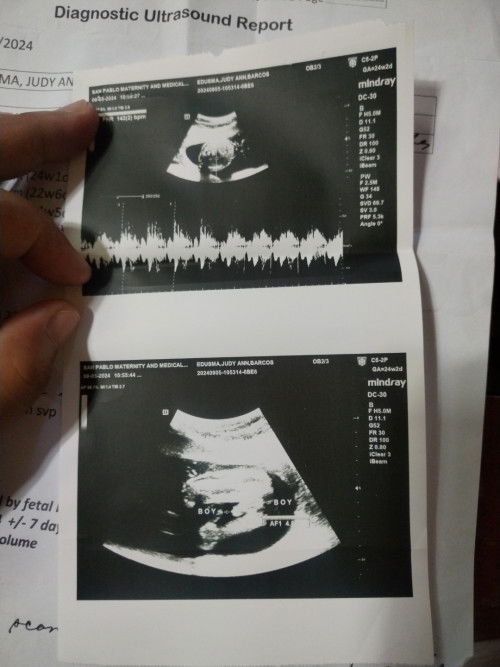

Excited na Ata lumabas baby ko 7 months Pala pero nasa baba na Siya.. Pang apat baby ko na Siya🥰

#excitdmommy